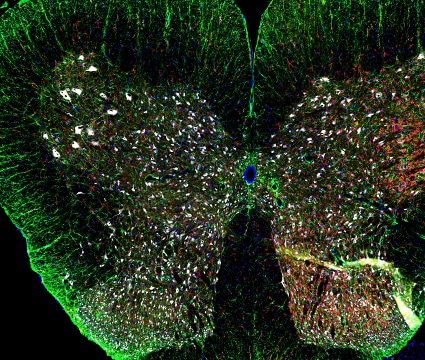

オールインワン蛍光顕微鏡『BZ-X800』 | キーエンス - Powered, オールインワン蛍光顕微鏡 BZ-X800:解析アプリケーション 体験版,

オールインワン蛍光顕微鏡 BZ-X800:解析アプリケーション 体験版, 大阪大学 創薬サイエンス研究支援拠点,

大阪大学 創薬サイエンス研究支援拠点, すべてを鮮明に。次元を超えた解析力 オールインワン蛍光顕微鏡,

すべてを鮮明に。次元を超えた解析力 オールインワン蛍光顕微鏡,![Yahoo!オークション - [SK][G6662-B] KEYENCE キーエンス BZ Yahoo!オークション - [SK][G6662-B] KEYENCE キーエンス BZ](https://auctions.c.yimg.jp/images.auctions.yahoo.co.jp/image/dr000/auc0408/users/02c06dcde52066aba3322636e896f31c3da3e366/i-img1200x797-1690880060vd3f8i2063017.jpg) Yahoo!オークション - [SK][G6662-B] KEYENCE キーエンス BZ,

Yahoo!オークション - [SK][G6662-B] KEYENCE キーエンス BZ, 従来の半額の予算から導入できる!?オールインワン蛍光顕微鏡,

従来の半額の予算から導入できる!?オールインワン蛍光顕微鏡, 暗室不要でクリアな蛍光観察。ウェルすべてを一括解析できる蛍光,

暗室不要でクリアな蛍光観察。ウェルすべてを一括解析できる蛍光, オールインワン蛍光顕微鏡 BZ-X シリーズ | キーエンス,

オールインワン蛍光顕微鏡 BZ-X シリーズ | キーエンス, キーエンス オールインワン蛍光顕微鏡買取 | 顕微鏡買取ドット,

キーエンス オールインワン蛍光顕微鏡買取 | 顕微鏡買取ドット, キーエンスより1台であらゆる観察に対応できる蛍光顕微鏡が新,

キーエンスより1台であらゆる観察に対応できる蛍光顕微鏡が新, Yahoo!オークション - KEYENCE キーエンス Biozero 蛍光顕微鏡,

Yahoo!オークション - KEYENCE キーエンス Biozero 蛍光顕微鏡, 資料ダウンロード | 顕微鏡観察ラボ | キーエンス

資料ダウンロード | 顕微鏡観察ラボ | キーエンス